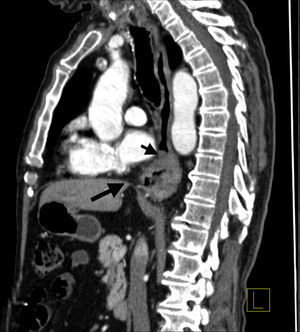

Presentamos el caso de un varón de 86 años en el que destacaba hipertensión arterial y un ictus con secuelas leves hacía 15 años, que fue diagnosticado de adenocarcinoma HER ii positivo en esófago distal. En el TC toracoabdominal no se observaron metástasis, infiltración de órganos adyacentes o adenopatías patológicas. El paciente tenía una voluminosa hernia de hiato (fig. 1). En la primera ecoendoscopia no se pudo franquear la estenosis esofágica maligna. El ecocardiograma inicial mostró una fracción de eyección ventricular (FEV) del 61%.